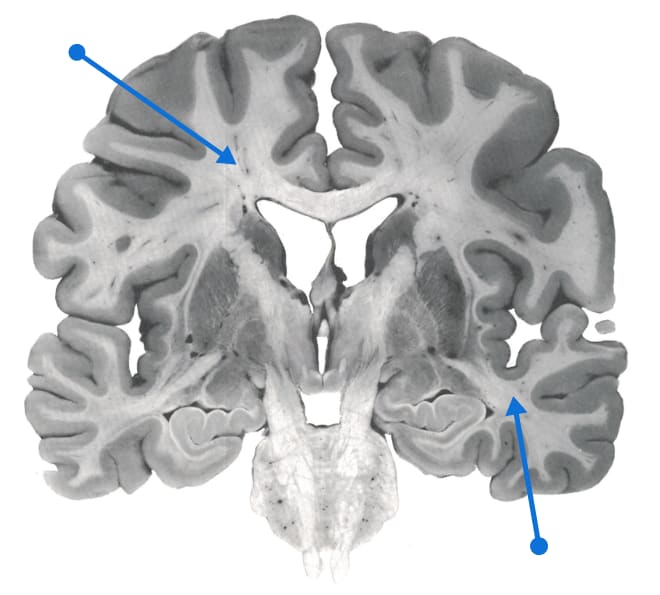

Massive cerebral prosthetic connectivity

Source: https://www.neuromedia.ca/white-matter/

Half of the human brain is white matter, i.e. neuronal axons with fatty sheaths around them to make them transmit signals faster. White matter is ~1/10 the volume of rodent brains, but ~1/2 the volume of human brains. Wiring is expensive and gets minimized; see “Principles of Neural Design” by Sterling and Laughlin. All these long-range axons are a huge metabolic expense. That means fast, long-range, high bandwidth (so to speak——there are many different points involved) communication is important to cognitive capabilities. See here.